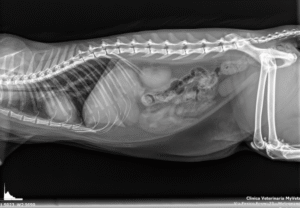

L’esame radiografico è uno step fondamentale nell’indagine diagnostica di base. La clinica è dotata di un apparecchio radiografico digitale diretto ad alta risoluzione che consente di ottenere immagini dettagliate e visualizzate istantaneamente, riducendo così il tempo di esecuzione dell’esame e risparmiando stress al pazienti.

Le imm

agini vengono archiviate nel nostro database e possono essere trasmesse per via telematica.